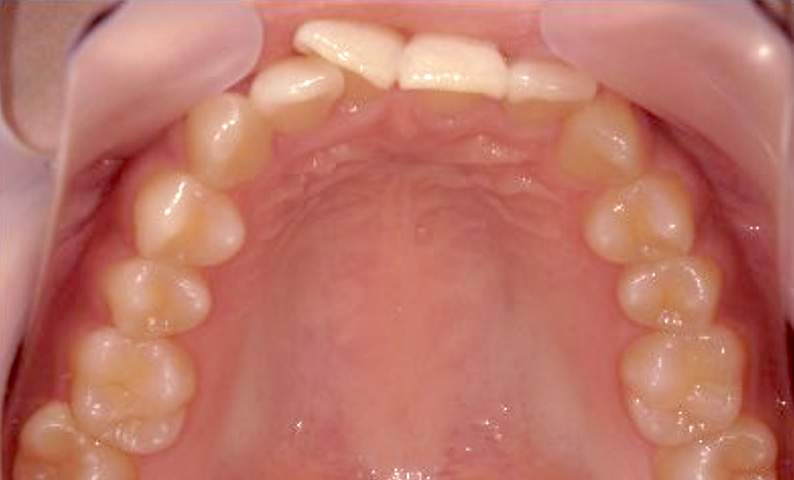

症例_024 上顎だけの部分矯正

治療期間:7ヶ月金額:30万円+税女性前歯のガタガタ上の前歯だけ

| Before | After |